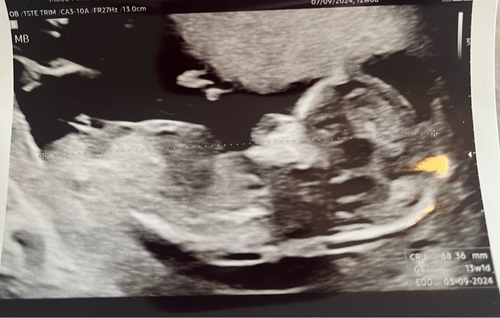

Ik zet hem voor de zekerheid ook even in deel 2! 13 weken en 2 dagen op deze echo ❤️

Ik zet hem voor de zekerheid ook even in deel 2! 13 weken en 2 dagen op dez ...

Helaas geen nub te zien